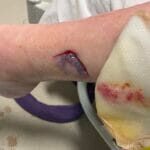

Enrolled Nurse (EN): Permitted Procedures

This page provides a quick reference of Care Plans and Tutorials available on The Wound Sandwich (TWS) which are permitted to be undertaken by staff with a Enrolled Nurse (EN) qualification. Additional applicable qualifications are also listed.